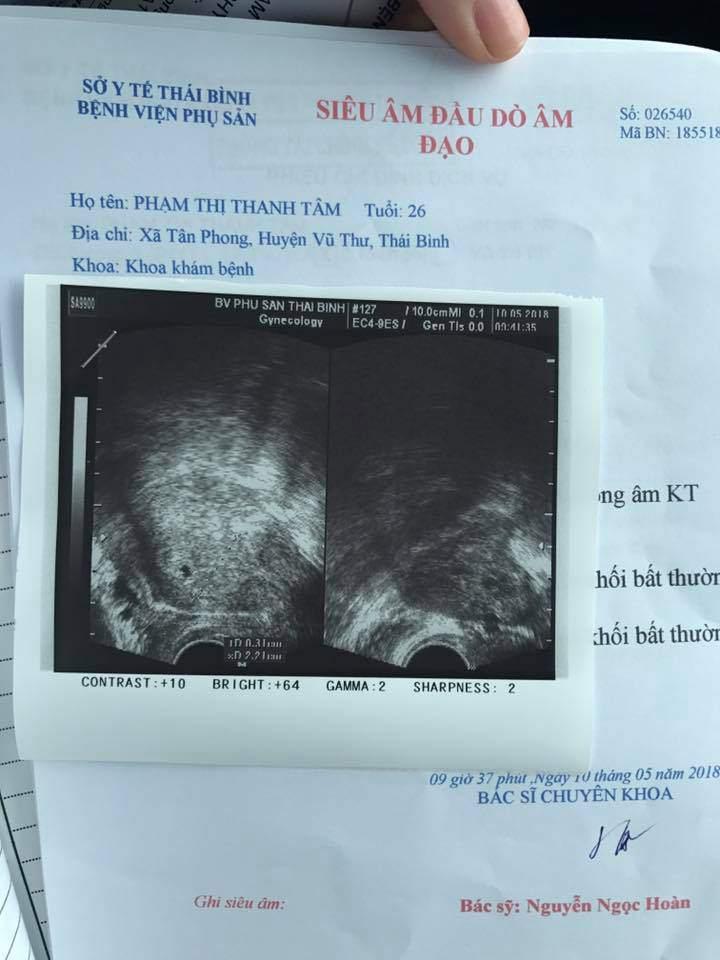

Mẹ nuôi Yến Nhi hiện đã có bầu được khoảng 3 tuần, em bé mới là một phôi thai hơn 3mm và dự sinh đầu năm 2019.